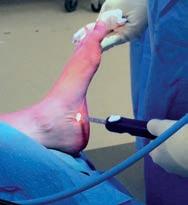

Cancer experts are trying to change the narrative on the unwanted side effects from prostate cancer treatment.

It was once the inevitable collateral damage from prostate cancer treatment – the lifechanging side effects that were considered the price that men had to pay to beat the disease.

Incontinence and erectile dysfunction (ED) have often been the unwanted legacy of radical surgery and radiation treatment, associated with poor rates of recovery.

That includes innovative rehabilitative techniques and penile implants, as well as a new technique which has been used in Melbourne to restore erectile function by removing sural nerves from the patient’s leg and grafting them for use in the penis.

However, Dr Sofield said there were now good treatments available to restore sexual health, with multidisciplinary rehab programs for men after surgery, using nonsurgical treatment.

“I refer people to these programs, which see men pre-operatively and plan ahead, and within weeks of surgery they can be on a penile rehab program,” he said.

“And at the end of that process, if conservative options fail, one to two years after surgery, then they might come back and we look at the last option, which is a surgical implant.

Her clinic recently launched an online men’s health platform in conjunction with LTR Pharma, which provides telehealth consultations and access to drug treatments, including the erectile dysfunction nasal spray Spontan, which can now be prescribed online to eligible patients through the TGA’s early access scheme.

“Guys need to know there are lots of options, but whatever you decide, you have to do rehab, whether it’s a sural graft or an implant, you have to think about it along the lines that if you were getting a hip replacement you’d go to the gym and get the exercises from the physio, and you have to do the same for the penis.”